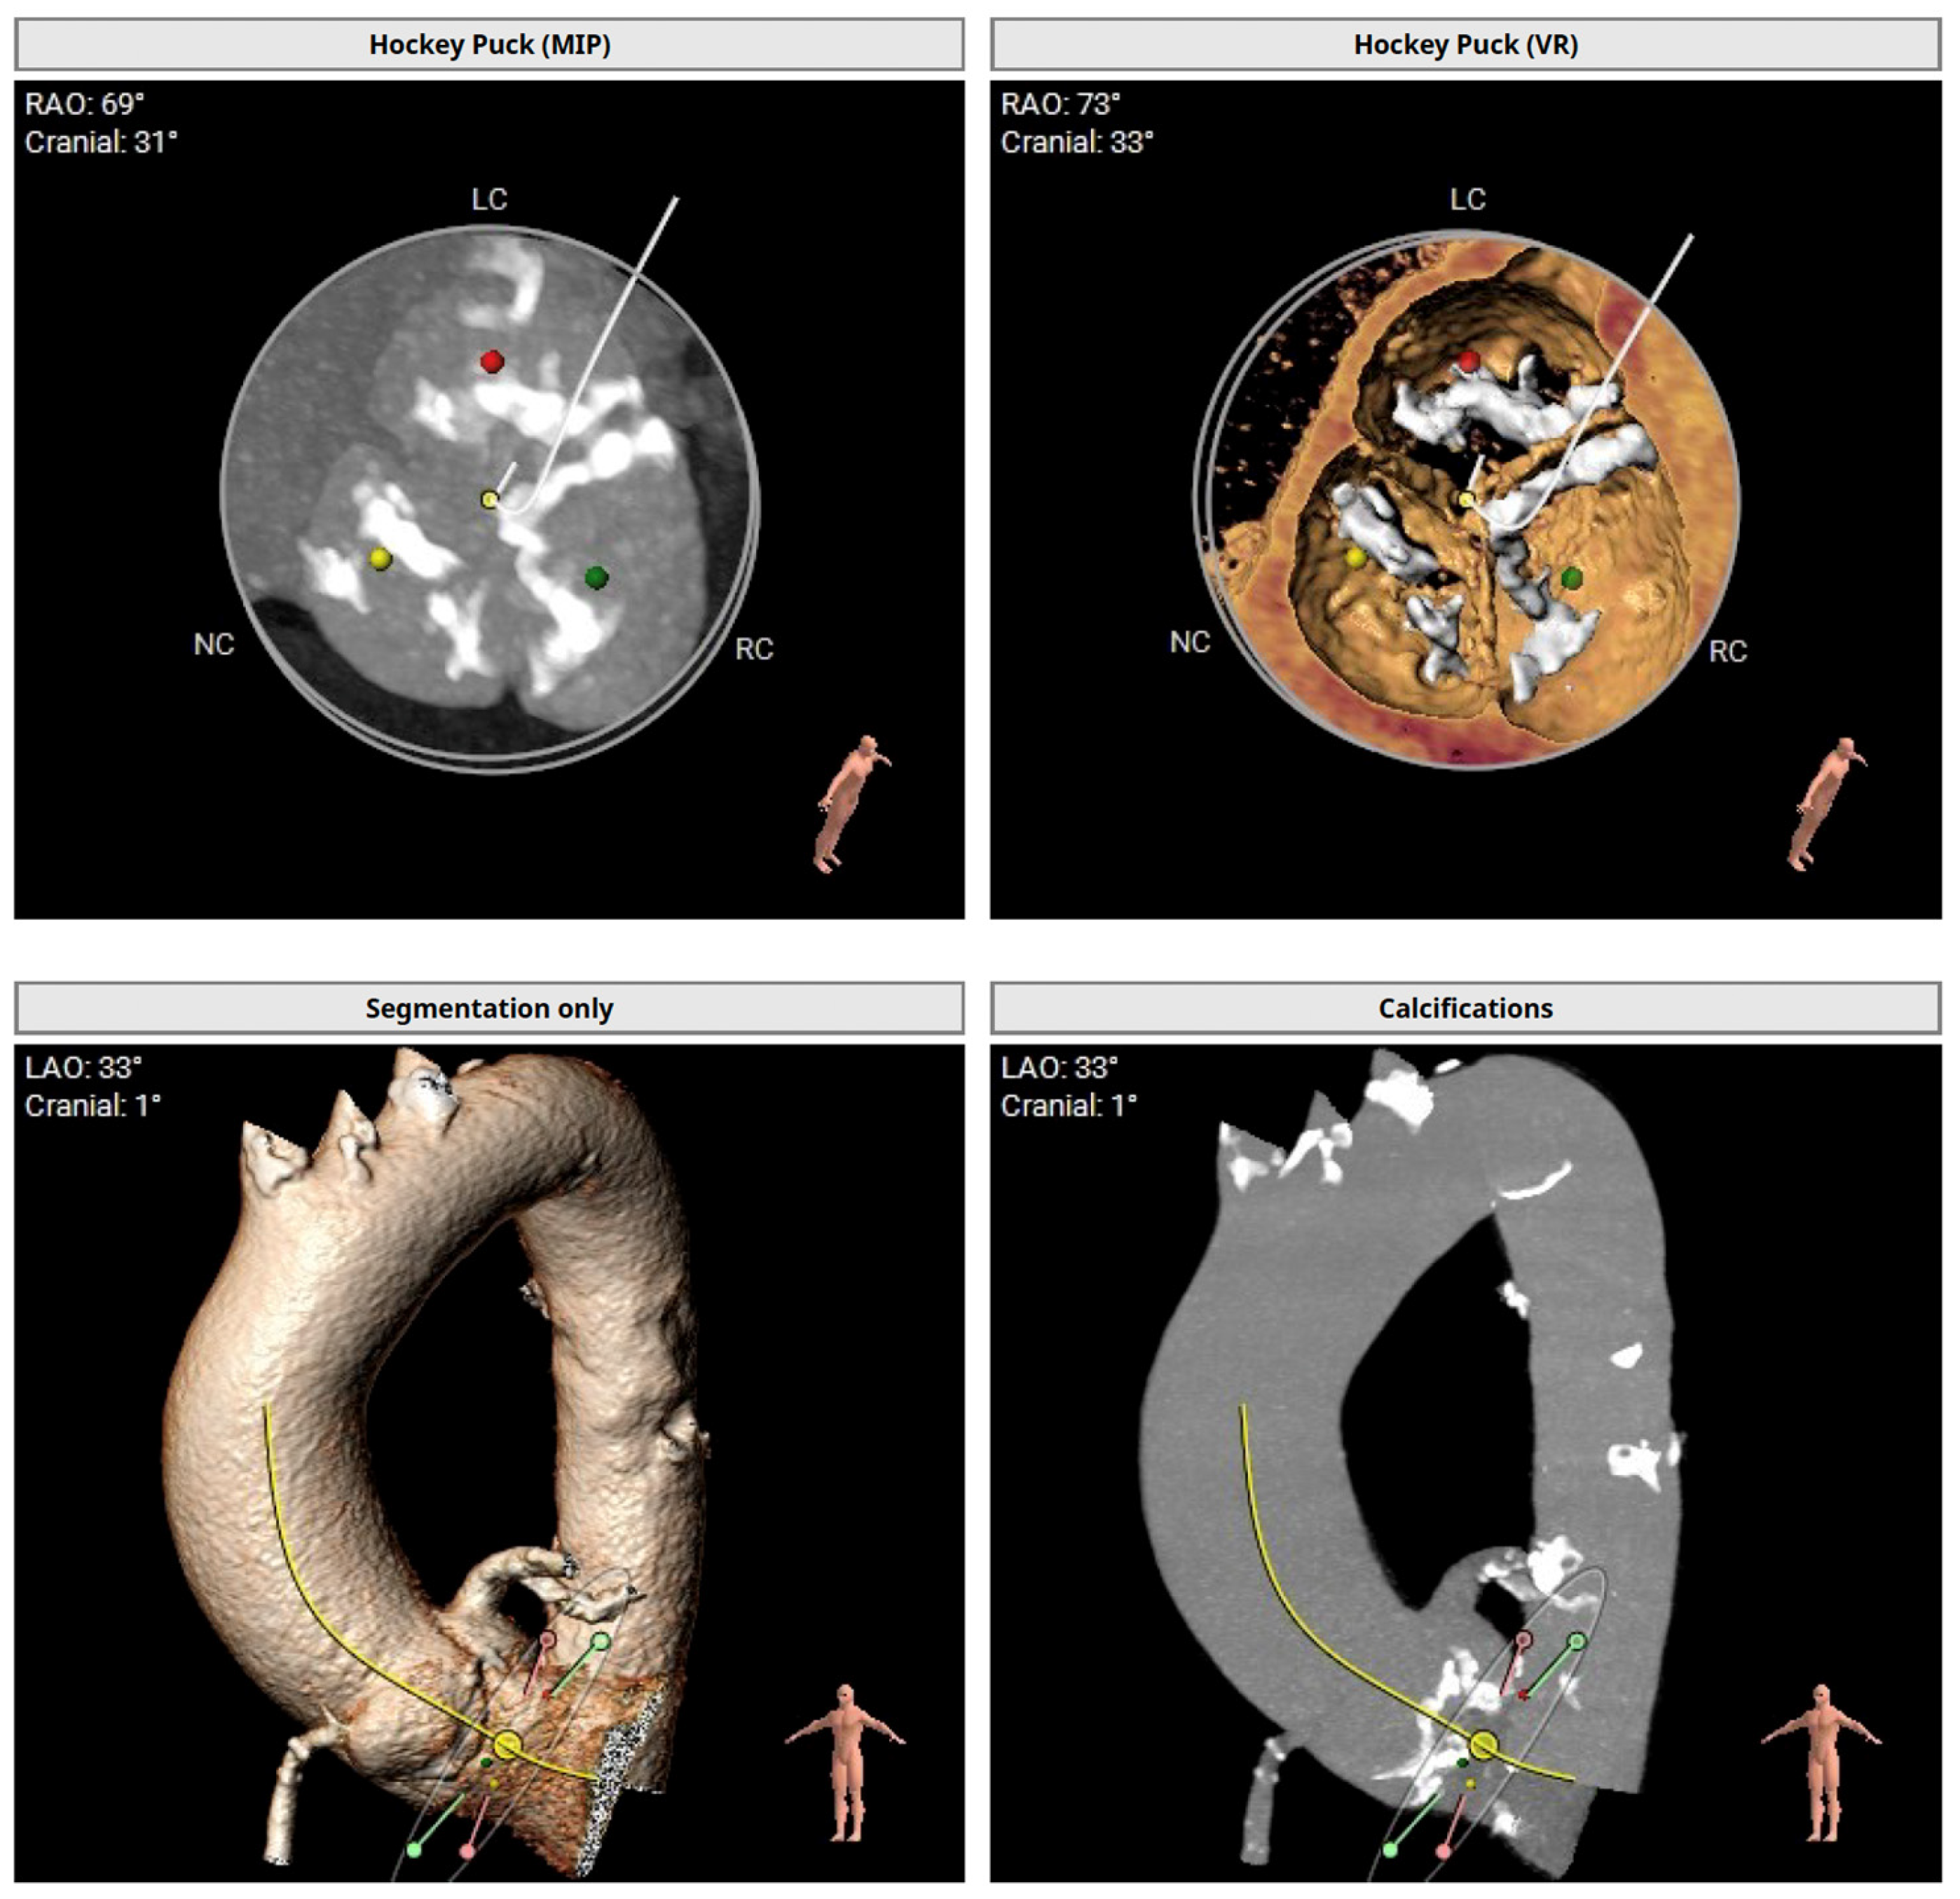

The preprocedural TAVI-CT showed an asymmetric calcium distribution with no calcification in the left ventricular outflow tract and a horizontal aortic annulus (Figure 1). With an average aortic annulus diameter of 24 mm and a maximum of 29 mm, the Evolut™ PRO+ 29 mm valve (Medtronic Cardiovascular, Minneapolis, MN, USA) was selected for the procedure.

Figure 1. Preprocedural transcatheter aortic valve implantation computed tomography with 3D volume rendering showing calcium distribution in the aorta and aortic valve calcification. LAO: Left anterior oblique projection; LC: Left coronary; MIP: Maximum intensity projection; NC: Noncoronary; RAO: Right anterior oblique projection; RC: Right coronary; VR: Virtual reality.